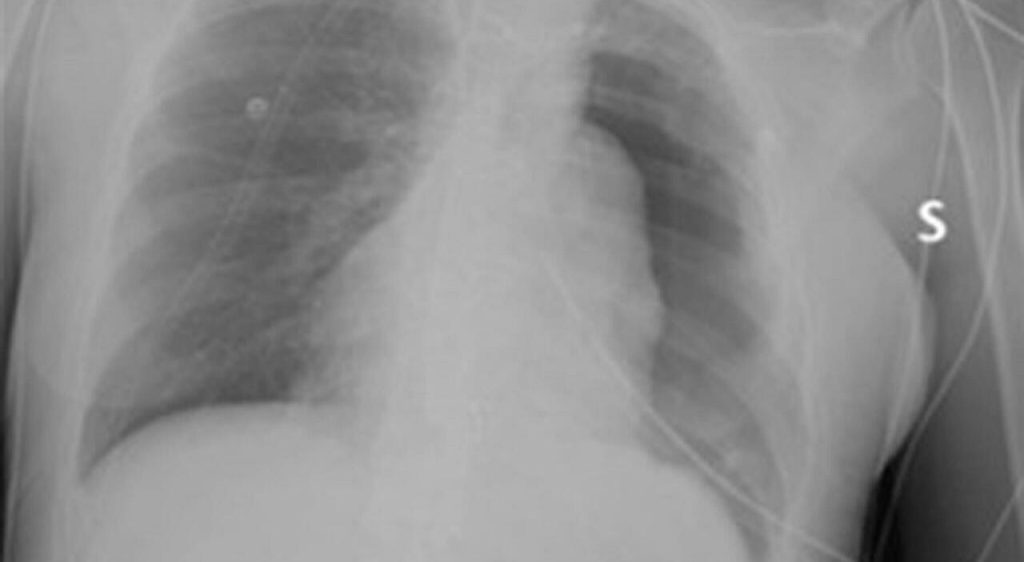

Dopo aver contratto il Covid-19, Sara ha notato un peggioramento delle sue condizioni respiratorie e si è sottoposta a una radiografia del torace, che ha rivelato la presenza di una massa voluminosa. Successive indagini hanno confermato il timoma, un tumore del timo che solitamente insorge in età adulta.

Sara (nome di fantasia) in seguito a un’infezione da Covid-19, notando un peggioramento delle sue condizioni respiratorie, affanno soprattutto da sforzo, dolore nella parte sinistra del torace, tosse secca stizzosa da tempo, si sottopone a una radiografia del torace. «La giovane donna presentava una massa molto voluminosa, che occupava tutta la parte centrale e la metà sinistra del torace», ricorda Maria Letizia Vita, dirigente medico presso la Uoc di Chirurgia toracica del Policlinico Gemelli.

«La massa occupava completamente l’emitorace sinistro, era fortemente adesa alla pleura parietale e inglobava l’atrio sinistro con le vene polmonari e l’arco aortico, Il polmone sinistro era completamente escluso e la massa comprimeva il cuore», ricorda il professor Stefano Margaritora, Ordinario di chirurgia Toracica all’Università Cattolica del Sacro Cuore. «Per l’estensione della neoplasia siamo dovuti ricorrere all’approccio chirurgico riservato agli interventi di cardiochirurgia maggiore, cioè attraverso una sterno- toracotomia sinistra». Margaritora conclude che «l’intervento è durato oltre 6 ore. Il recupero post-operatorio della paziente è stato eccellente».